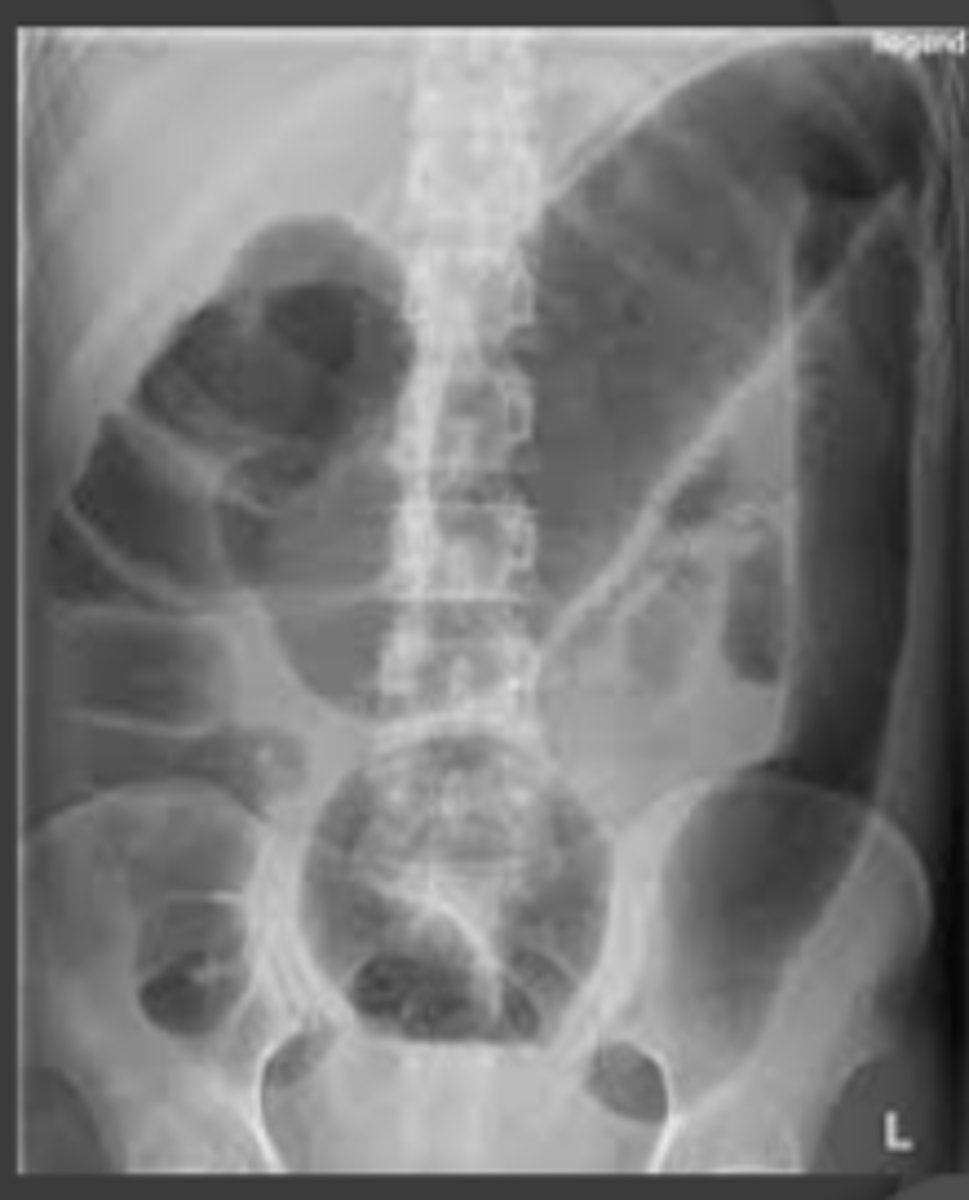

Toxic Megacolon X-Ray Figure

Increased toxic megacolon, colectomy, refractory to therapy, relapse

Increased toxic megacolon

Increased colectomy

Increased refractory to therapy, relapse